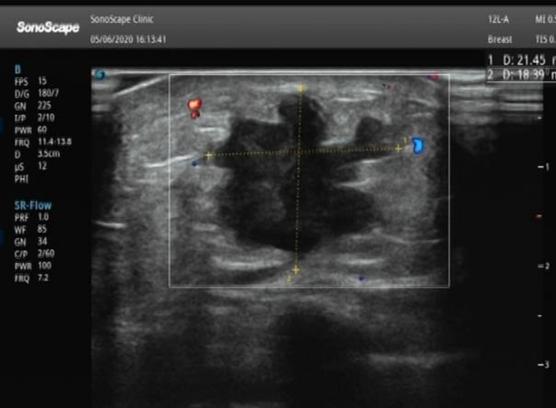

2、可区分囊性、实性肿块,对于实质性肿块的良恶性鉴别可以做初步诊断;

乳腺超声缺点

对钙化不敏感,尤其容易忽略砂砾样、点簇状的微钙化,而这些钙化往往提示肿块可能是恶性的。另外超声对非肿块性乳腺癌检出率低,容易漏诊。

超声适合所有需要进行乳腺检查的人,尤其适合育龄期女性。年轻女性大多是多腺体型,适合彩超检查,在进行彩超检查时,探头可以扫查到每个部位,因此,对于年轻、妊娠、哺乳期女性来说,超声可以作为首选的影像学检查方式。